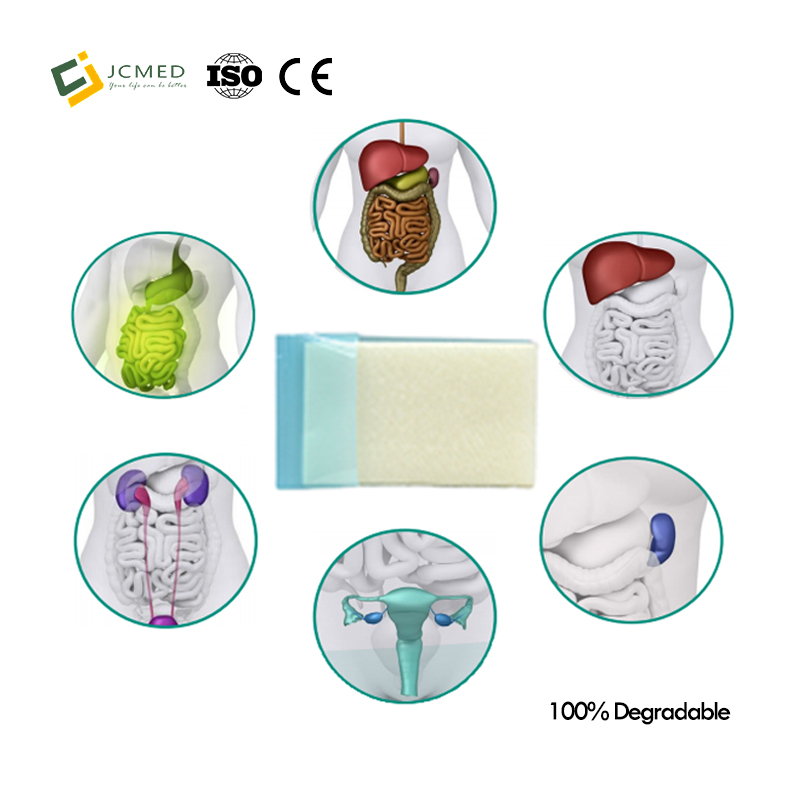

Application in various surgical procedures

General Surgery

Thoracic Surgery

heart

Obstetrics and Gynecology Neurosurgery

Urology

endoscopic surgery

orthopedics